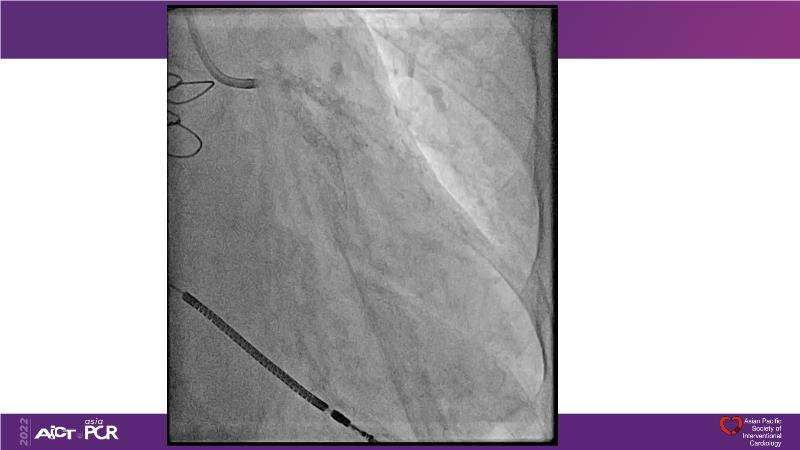

Cracking calcium: best practices to integrate intravascular lithotripsy into your calcium management algorithm

With this session, keep up to date on the evidence, trials and outcome data for intravascular lithotripsy in severely calcified lesions. Learn how to use this technique in real-world patients and understand its role in the treatment algorithm for severely calcified coronary lesions.